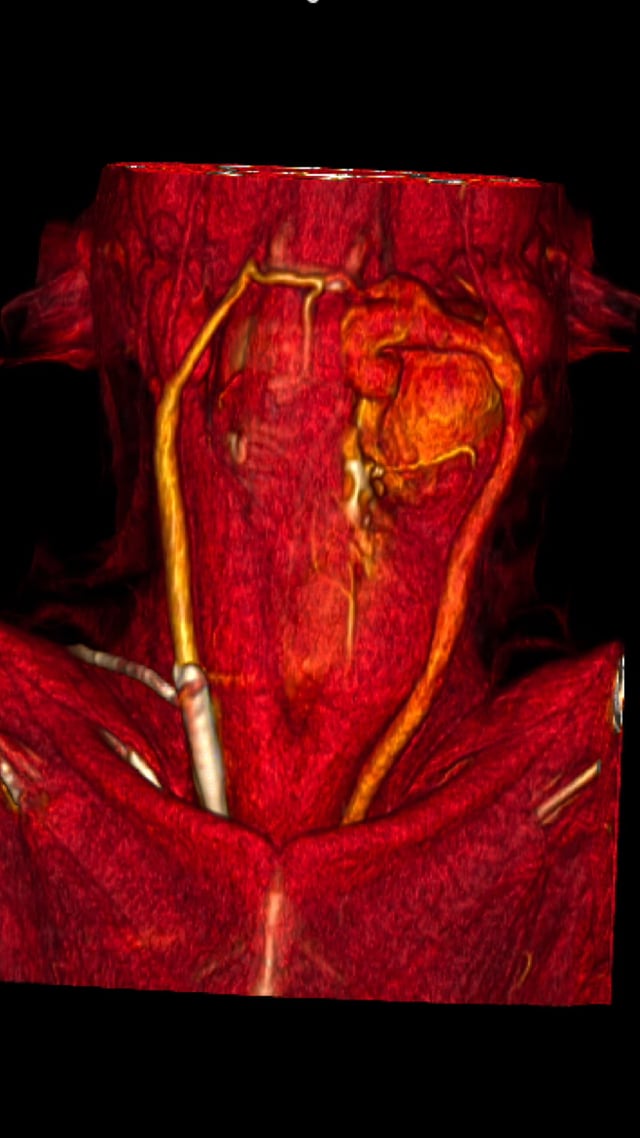

Palestra 'Desafios cirúrgicos: tumores hepáticos' no Animal Health Expo+Congress.